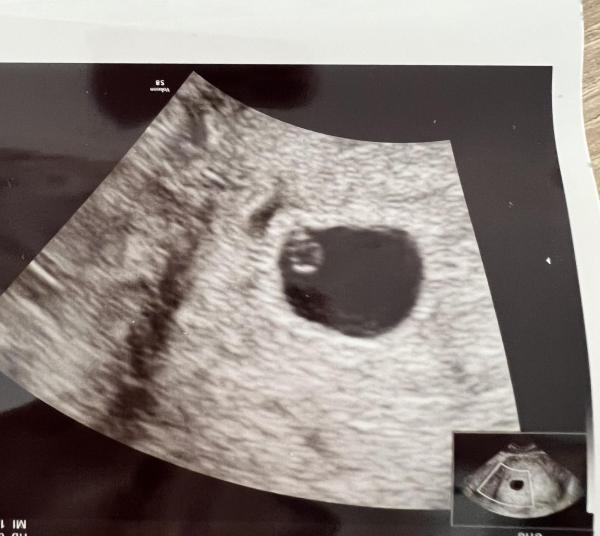

Ich bin mir nicht sicher, vielleicht kann mir jemand helfen und kennt sich aus...ob junge oder mädchen

Bild zu Ramzi Methode hilfe - Schwanger - wer noch? Rund um die Schwangerschaft

Junge , bin mir zu 50% sicher